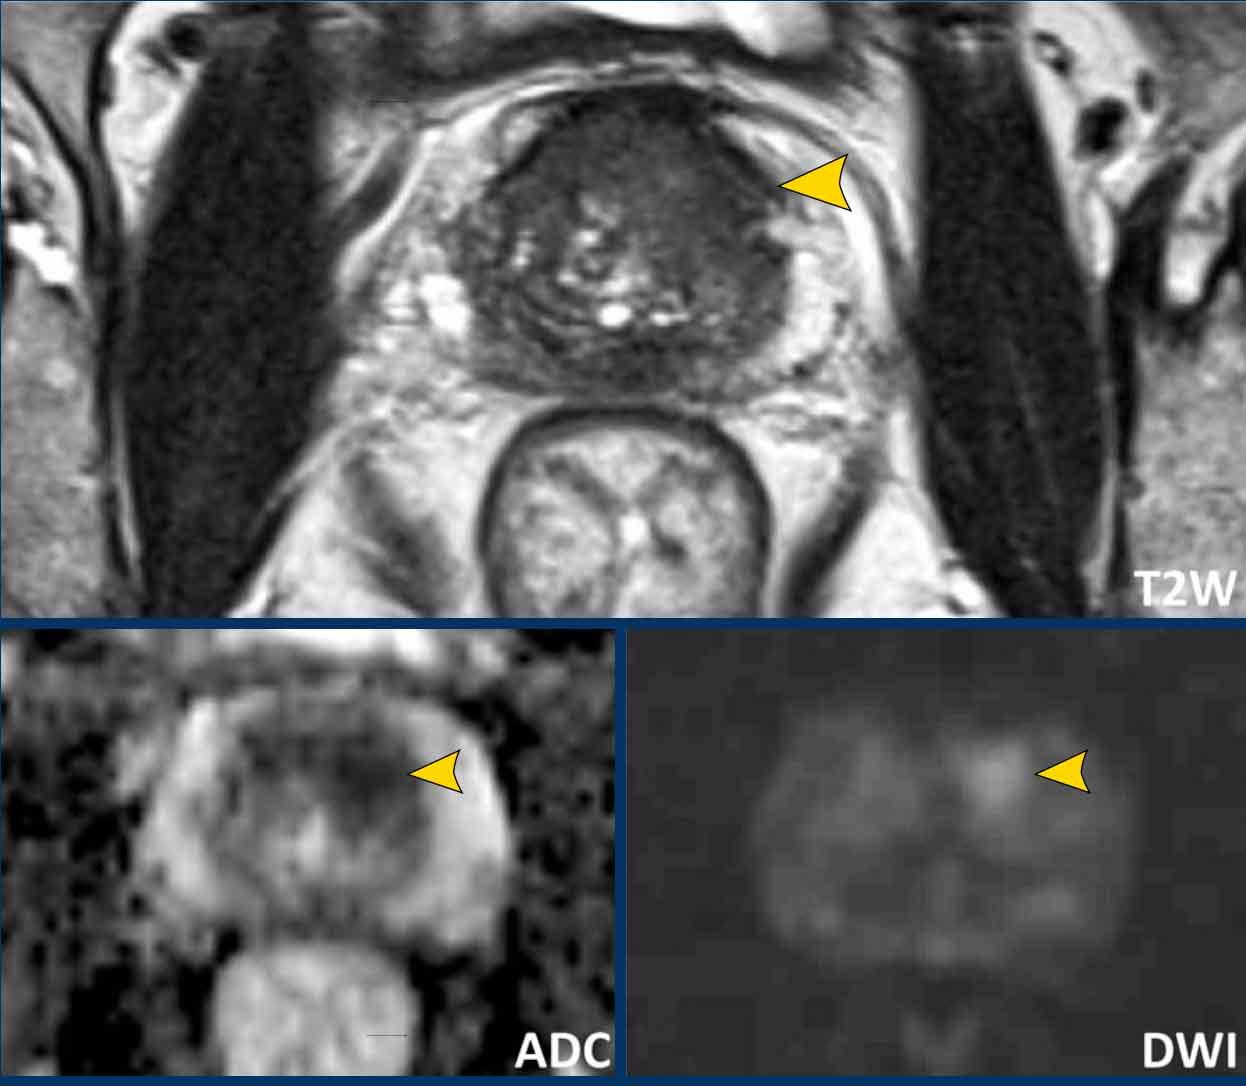

Các phát hiện bao gồm:

- Một tổn thương kích thước 17 mm (không hiển thị phép đo) nằm ở vùng ngoại vi, phía sau bên trái của phần giữa tuyến tiền liệt.

- Giảm tín hiệu rõ rệt trên ADC và tăng tín hiệu rõ rệt trên DWI.

- Tương ứng với vùng giảm tín hiệu trên chuỗi xung T2W.

- Trên chuỗi xung T2W, tổn thương tiếp xúc diện rộng với vỏ bao tuyến tiền liệt.

Tổn thương này được xếp vào phân loại PI-RADS 5 với nghi ngờ xâm lấn ra ngoài tuyến tiền liệt.

Điểm Gleason là 4+3.

Tổn thương nghi ngờ này có hạn chế khuếch tán đáng kể.

Giá trị ADC đo được là 440 mm²/s.

Giá trị ADC thấp cho thấy nguy cơ ác tính cao hơn.

Giá trị ADC thực tế có tương quan nghịch với khả năng ác tính có ý nghĩa lâm sàng.

Các giá trị trên 900 mm²/s được coi là có khả năng lành tính và dưới 750 mm²/s có khả năng ác tính.

Tuy nhiên, kết quả định lượng có thể khác nhau đáng kể giữa các máy chụp và các giao thức chụp.